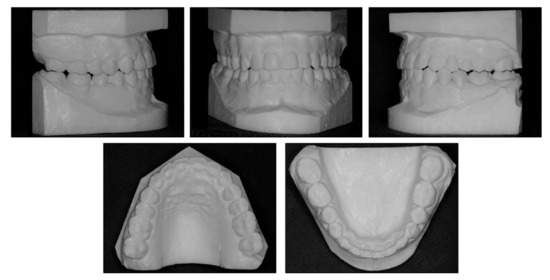

2.1. Diagnosis and Etiology

3. Results